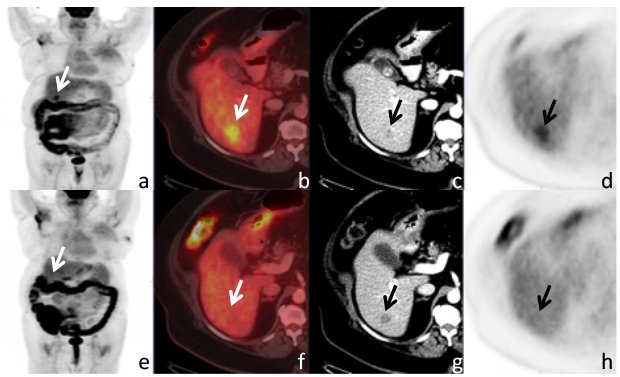

PET/CT preferred for monitoring metastatic breast tumors. http://ow.ly/Z3Bn30duhzV

#imaging#radiologypic.twitter.com/rcccddcuJc